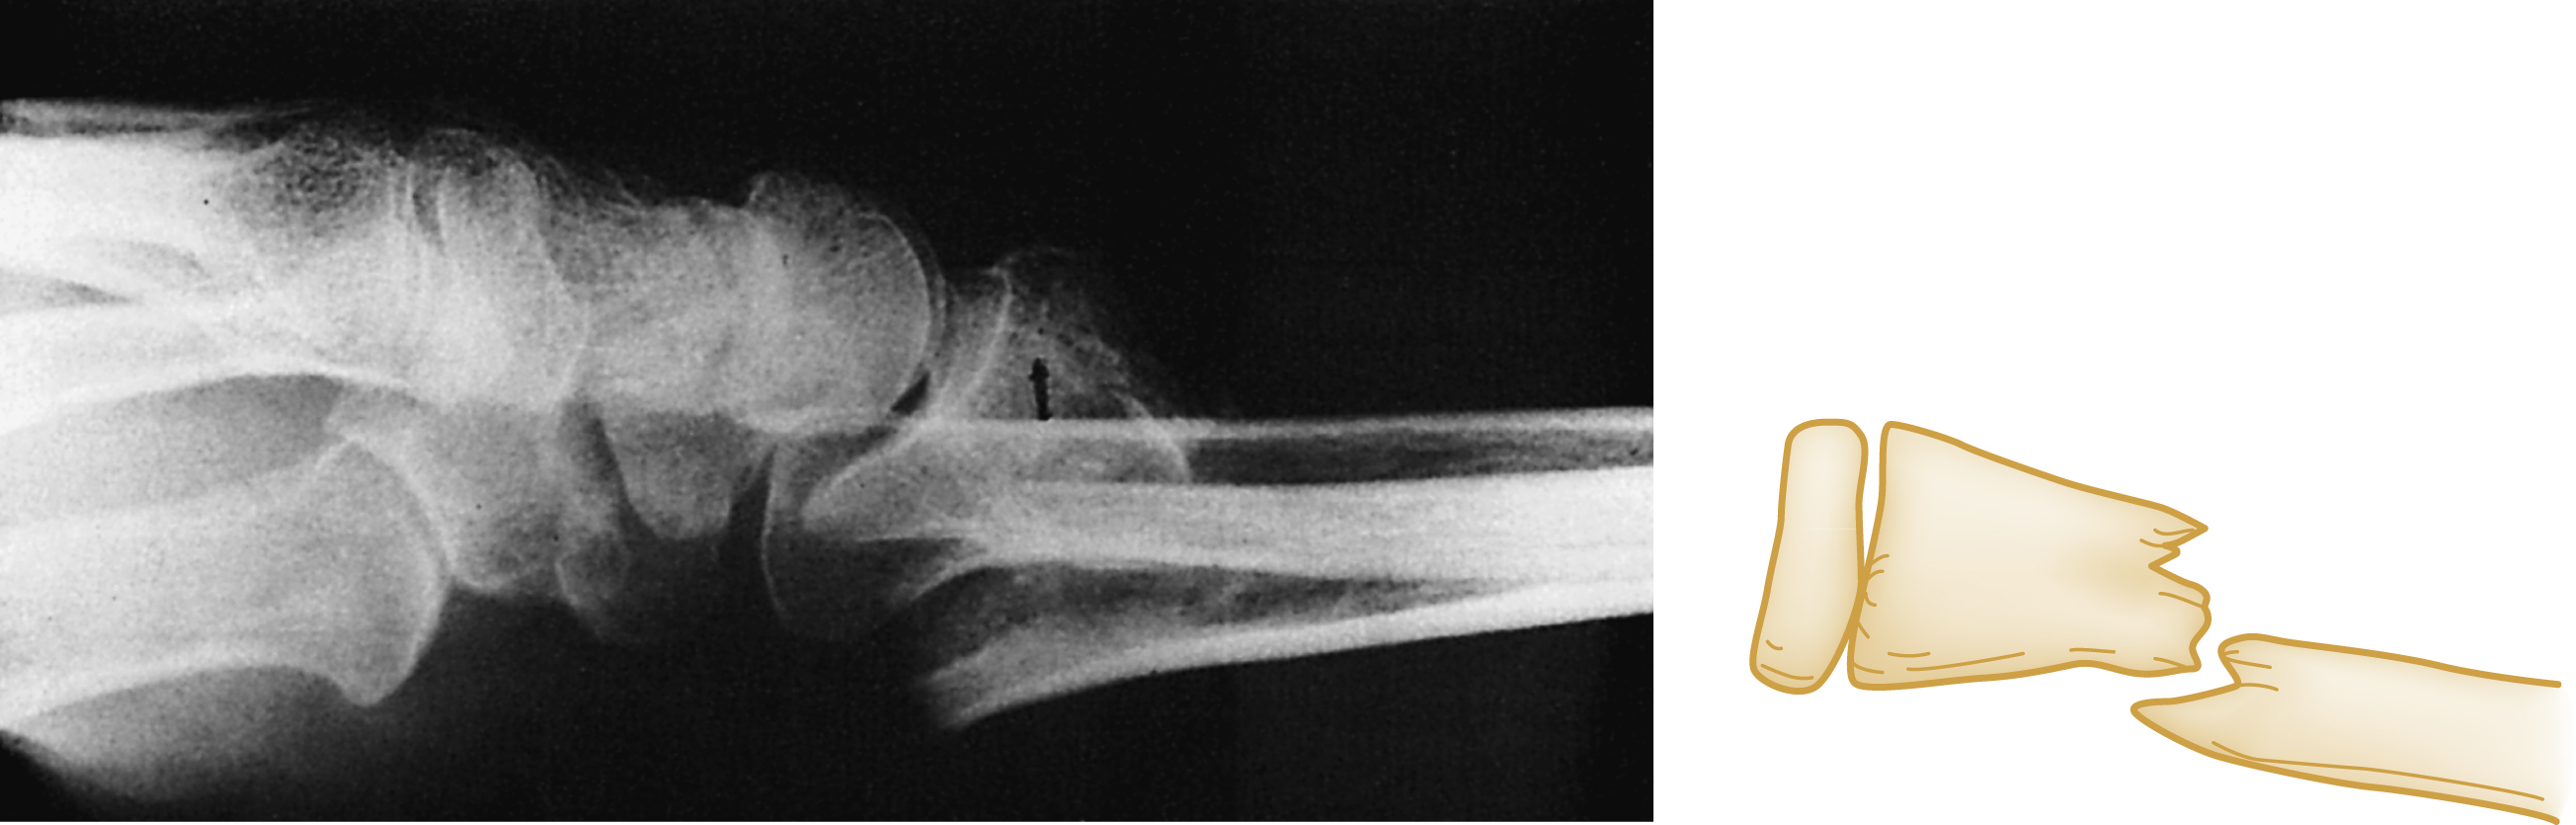

An additional modifier describes the direction of the fracture line in relation to the long axis of the bone in question. A transverse fracture occurs at a right angle to the long axis of the bone ( Fig. 41.1A ) whereas an oblique fracture runs oblique to the long axis of the bone (see Fig. 41.1B ). A spiral fracture results from a rotational force, a torque, and encircles the shaft of a long bone in a spiral fashion (see Fig. 41C ). The terms oblique and spiral are sometimes confused but can be important since the latter may have significance when child abuse is being considered as a mechanism of injury. A fracture with more than two fragments is termed comminuted (see Fig. 41.1D ).

Types of Fractures.

(A) Transverse. (B) Oblique. (C) Spiral. (D) Comminuted.

The position and alignment of the fracture fragments (i.e., their relationship to one another) should be described. Fragments are described relative to their normal position, and any deviation from normal is termed displacement. By convention, the position of the distal fragment is described relative to the proximal portion. Displacement may be described as a quantitative measurement (i.e., in millimeters) or as an approximate percentage of the bone width. It also may be described qualitatively as non, minimal, moderate, or severe. Fig. 41.2 shows dorsal displacement of the fractured radius, and Fig. 41.3 shows lateral, or valgus , displacement of the distal tibia and fibula.

Dorsal Displacement of Distal Radius.

Valgus Displacement of the Distal Tibia and Fibula.

The distal segment is angled away from the midline of the body. The arrow shows the location of the fracture and the valgus displacement of the distal segment.

The term avulsion fracture refers to a bone fragment that is pulled away from its normal position by the forceful contraction of a muscle ( Fig. 41.5A ) or the resistance of a tendon or ligament to a force in the opposite direction (see Fig. 41.5B ). The term impaction refers to the forceful collapse of one fragment of bone into or onto another. In the proximal humerus, this collapse typically occurs in a telescoping manner, particularly in older patients, whose bones are osteoporotic and brittle. In the tibial plateau, impaction occurs frequently in the form of a depression ( Fig. 41.6A and B ) and, in the vertebral bodies, impaction frequently occurs in the form of compression resulting in a significant loss of bone height in some cases (see Fig. 41.6C ).

(A and B) Tibial plateau fracture. (C) Vertebral body compression fracture (arrows) .